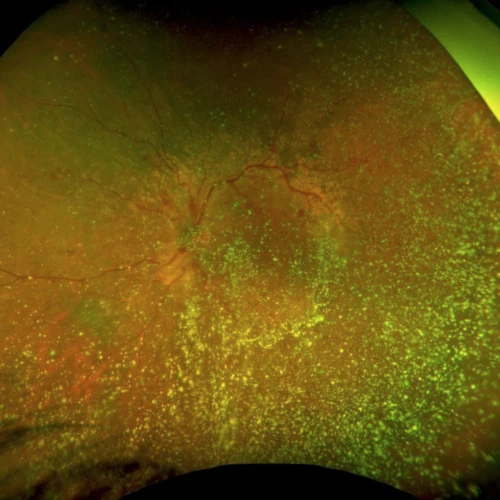

We are proud to announce our new fundus fluorescein angiogram available at our clinic. This allows us to provide full scope care for medical retina patients, including the treatment of AMD, diabetic retinopathy, and retinal vascular occlusions. Optos produces ultra wide-field images with a field of view up to 200 degrees, compared to standard angiogram images of around 70 degrees. This enlarged field of view influences the management of conditions that affect the peripheral retina, in particular diabetic retinopathy and vascular occlusions.